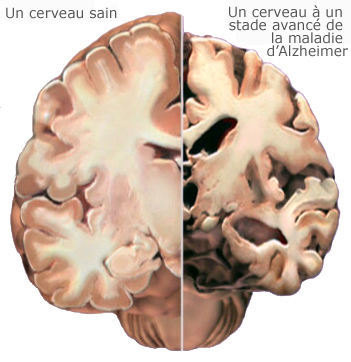

La source : journalmetro.com Cerveau Sain Vs Cerveau Atteint Dalzheimer Association

![]() La source : alz.org

La source : alz.org Aide Pour Alzheimer Et La Démence France Alzheimers